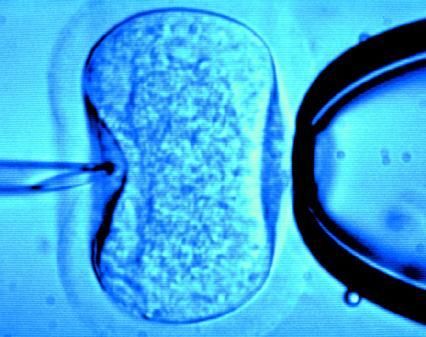

據英國《每日郵報》1月18日報道,英國一位60歲老婦將成為英國接受試管受精最年長者。這位老婦名叫蘇珊·托勒夫森,是一位退休教師,到今年10月她就滿60歲了。2008年,蘇珊曾去俄羅斯接受試管受精,在英國生下了她的第一個孩子。

倫敦哈利街的私人診所是英國試管嬰兒手術成功率較高的醫院之一,醫生們在上周一同意幫助蘇珊·托勒夫森進行第二次人工受孕。通常情況下,私人診所只在特殊情況下給50歲以上的婦女進行試管受精,例如,患者仍然有月經周期。這件事引起了絕經后婦女是否有生育權利的倫理大討論,現在要求提高生育治療年齡上限的呼聲越來越高。

現在,蘇珊·托勒夫森一家人很幸福,丈夫尼克·邁耶是一位公司經理,比她小11歲,他們的女兒今年2歲。專家表示,蘇珊很健康,她的女兒如果能有一個兄弟姐妹會更好,于是蘇珊想再次接受試管受精。《星期日郵報》獲悉,倫敦哈利街私人婦女診所的高級工作人員已經同意為蘇珊做試管受精,還決定幫助另一位57歲的老婦受孕。(海瀾)